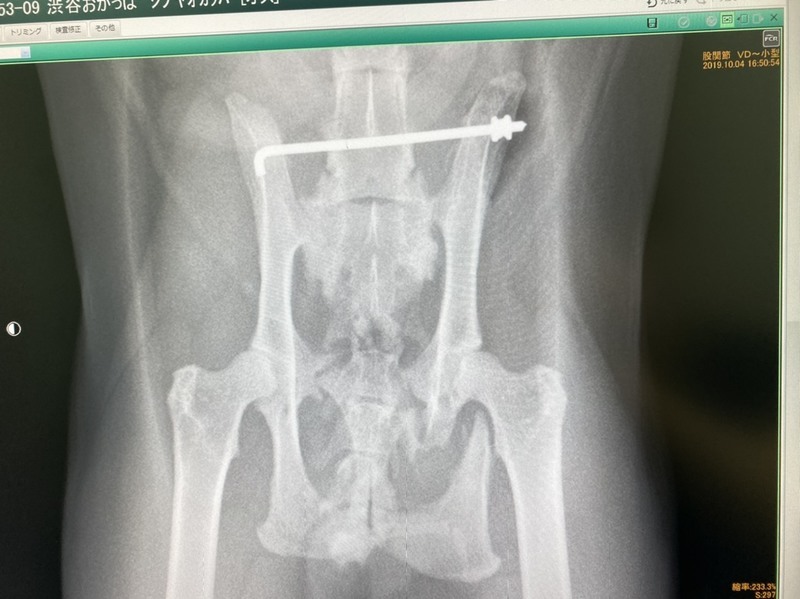

| 里親募集する理由 | 野良猫として長い間外で暮らしてきました。 運悪く事故にあい骨盤を骨折して歩けなくなっていた所をエサやりさんが発見し保護しました。 高額な医療費で手術出来ないまま放置されていたので引き取りました。 何とか寄付を集め手術も無事終わり歩けるようになりました。 |